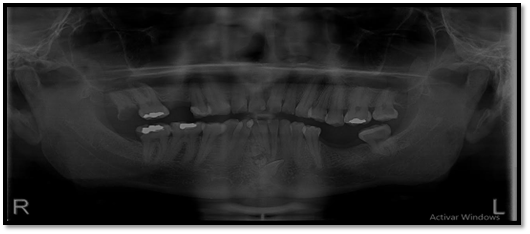

El órgano dentario retenido tiene una dirección mesioangular, sobrepasando la corona la mitad de la línea media. En íntima relación se encuentra las raíces de los órganos dentarios 4.1; 3.1; 3.2 con los dentículos y adicionándose con la relación del órgano dentario retenido esta la raíz del órgano dentario.

Imagen 3. Radiograficas Peiapical.

El diagnóstico y tratamiento oportuno que se debe tener frente a las neoplasias odontogénicas que son frecuentes en la consulta odontológica, y la mayoría de casos pasa desapercibido nos hacen tomar conciencia de lo importante de tratar , guiar a los pacientes que visitan la unidad de atención odontológica Uniandes a realizarse exámenes complementarios, radiográficos panorámicos, periapicales, oclusales que tienen la posibilidad de demostrar una visión más clara de las estructuras dentarias vecinas, previniendo desarrollos o formaciones de neoplasias ya que, las radiografías las intraorales periapicales, oclusales demuestra mayor fidelidad dimensional en comparación a la panorámica detectando oportunamente patologías que son asintomáticas.

En su gran mayoría en la presentación de este caso clínico se puede observar la presencia de una sombra radiopaca que concuerdan con el órgano dentario retenido 4.2.con una imagen mixta con múltiples radiopacidades muy similares a los órganos dentarios que están rodeados de un halo radiolúcido perimetral que son similares descripciones de investigaciones de otros autores.

Los exámenes radiográficos son de gran valor en el diagnóstico oportuno de neoplasias odontógenas principalmente las de mayor fidelidad como las radiografías periapicales y oclusales.